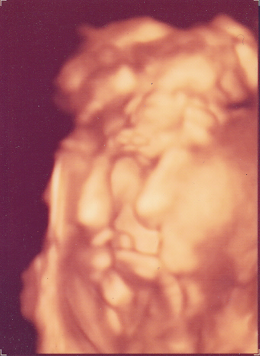

I remember gazing at the 3D ultrasound of my son, which I decided to frame a few days after receiving it. I suppose another person would have found it difficult to make out what was what, exactly, in that image. But I could see him clear as day, nestled there snuggly, my long sought after Nathaniel (“Gift from God”). That moment inspired the two “Nathaniel” paintings you can find in the gallery.

I couldn’t think of a more worthy subject matter. I began seeking ultrasound images from friends and family, to share with them my attempts to capture a bit of the magic and joy of life, in utero. Please contact me if you or a loved one would enjoy a similarly commissioned work.